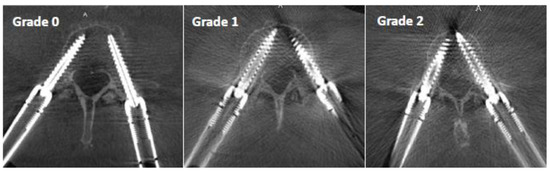

- Grade 0: screw within the pedicle without cortical breach;

- Grade 1: 0–2 mm breach, minor perforation, including cortical encroachment;

- Grade 2: 2–4 mm breach, moderate breach;

- Grade 3: >4 mm breach, severe displacement, which was not found in this cohort.